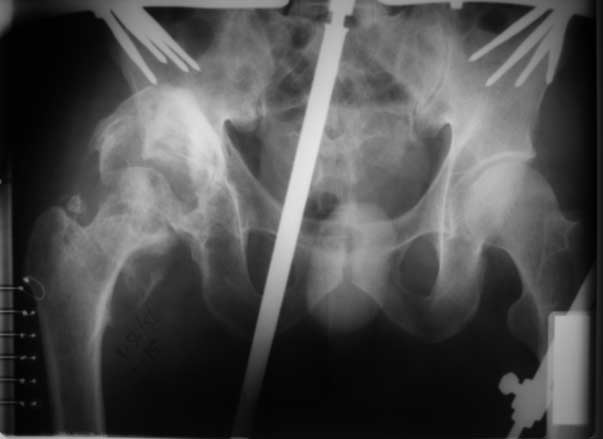

Застарелый вывих бедра (продолжение темы)

репозиция 3 нед, артропластика Corail-Duraloc